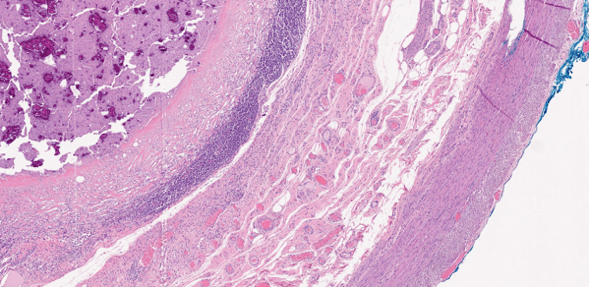

The appendiceal lumen is swollen and filled with mucinous material that contains food debris and calcifications. The wall appears flattened, with loss of the epithelial lining. The submucosa shows fibrosis and moderate lymphocytic infiltration. The muscularis propria is heavily infiltrated with inflammatory cells. Mucinous material is not present within the appendiceal wall, and no epithelial dysplasia is observed (Fig 3.)